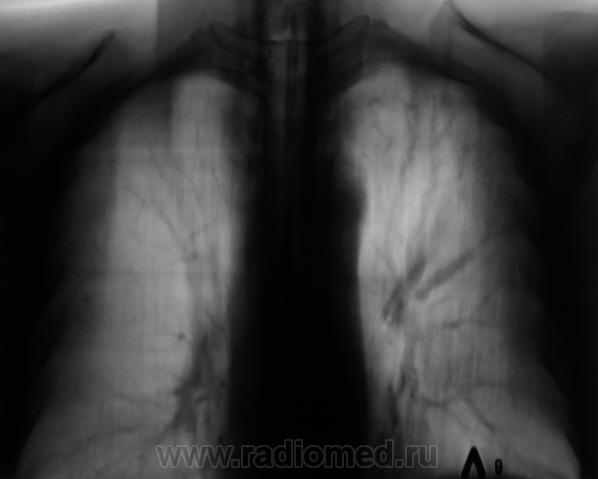

При расшифровке флюорограмм пациент "взят на контроль". Жалоб пациент не предъявляет. Подняли "архив", флюорограмма за 2009 г. - "норма".

Произвели стандартное дообследование.

tbc

А, какой ТВС?